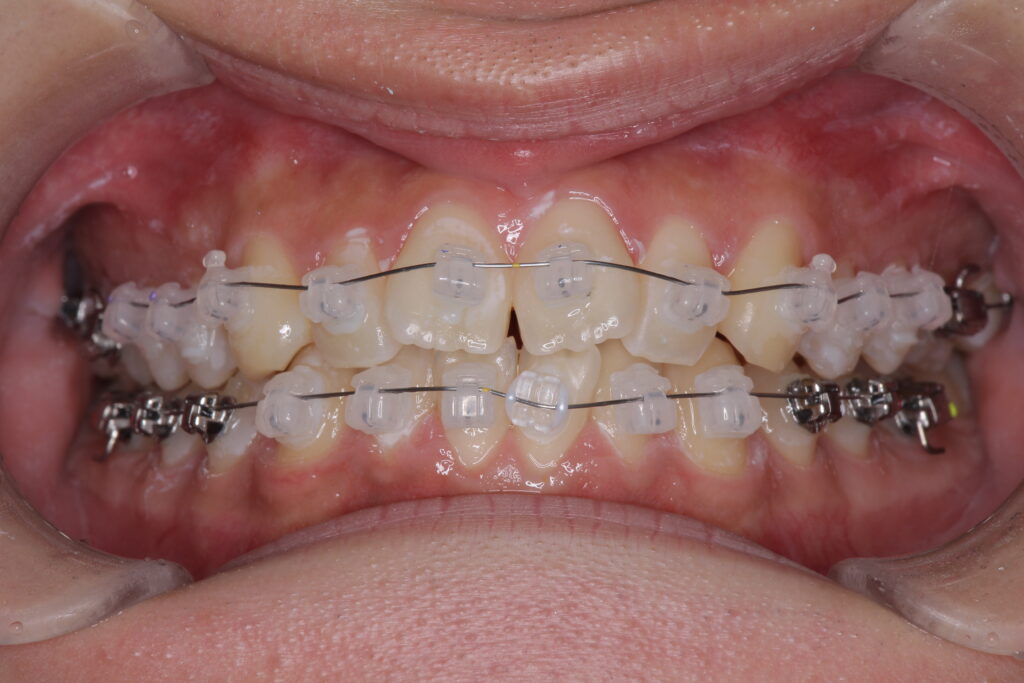

本格的な矯正治療とはマルチブラケットと呼ばれるブラケット+ワイヤーを用いた方法やマウスピース型の装置を使用する方法などがありますが、大人の歯(永久歯)を積極的に動かすことでかみ合わせの能力を高めることを目的としています。

参考症例:受け口を一期治療で治療したケース(7歳で開始し、8ヶ月の一期治療を実施)